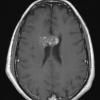

VASCULAR

Cavernous Angioma (13)